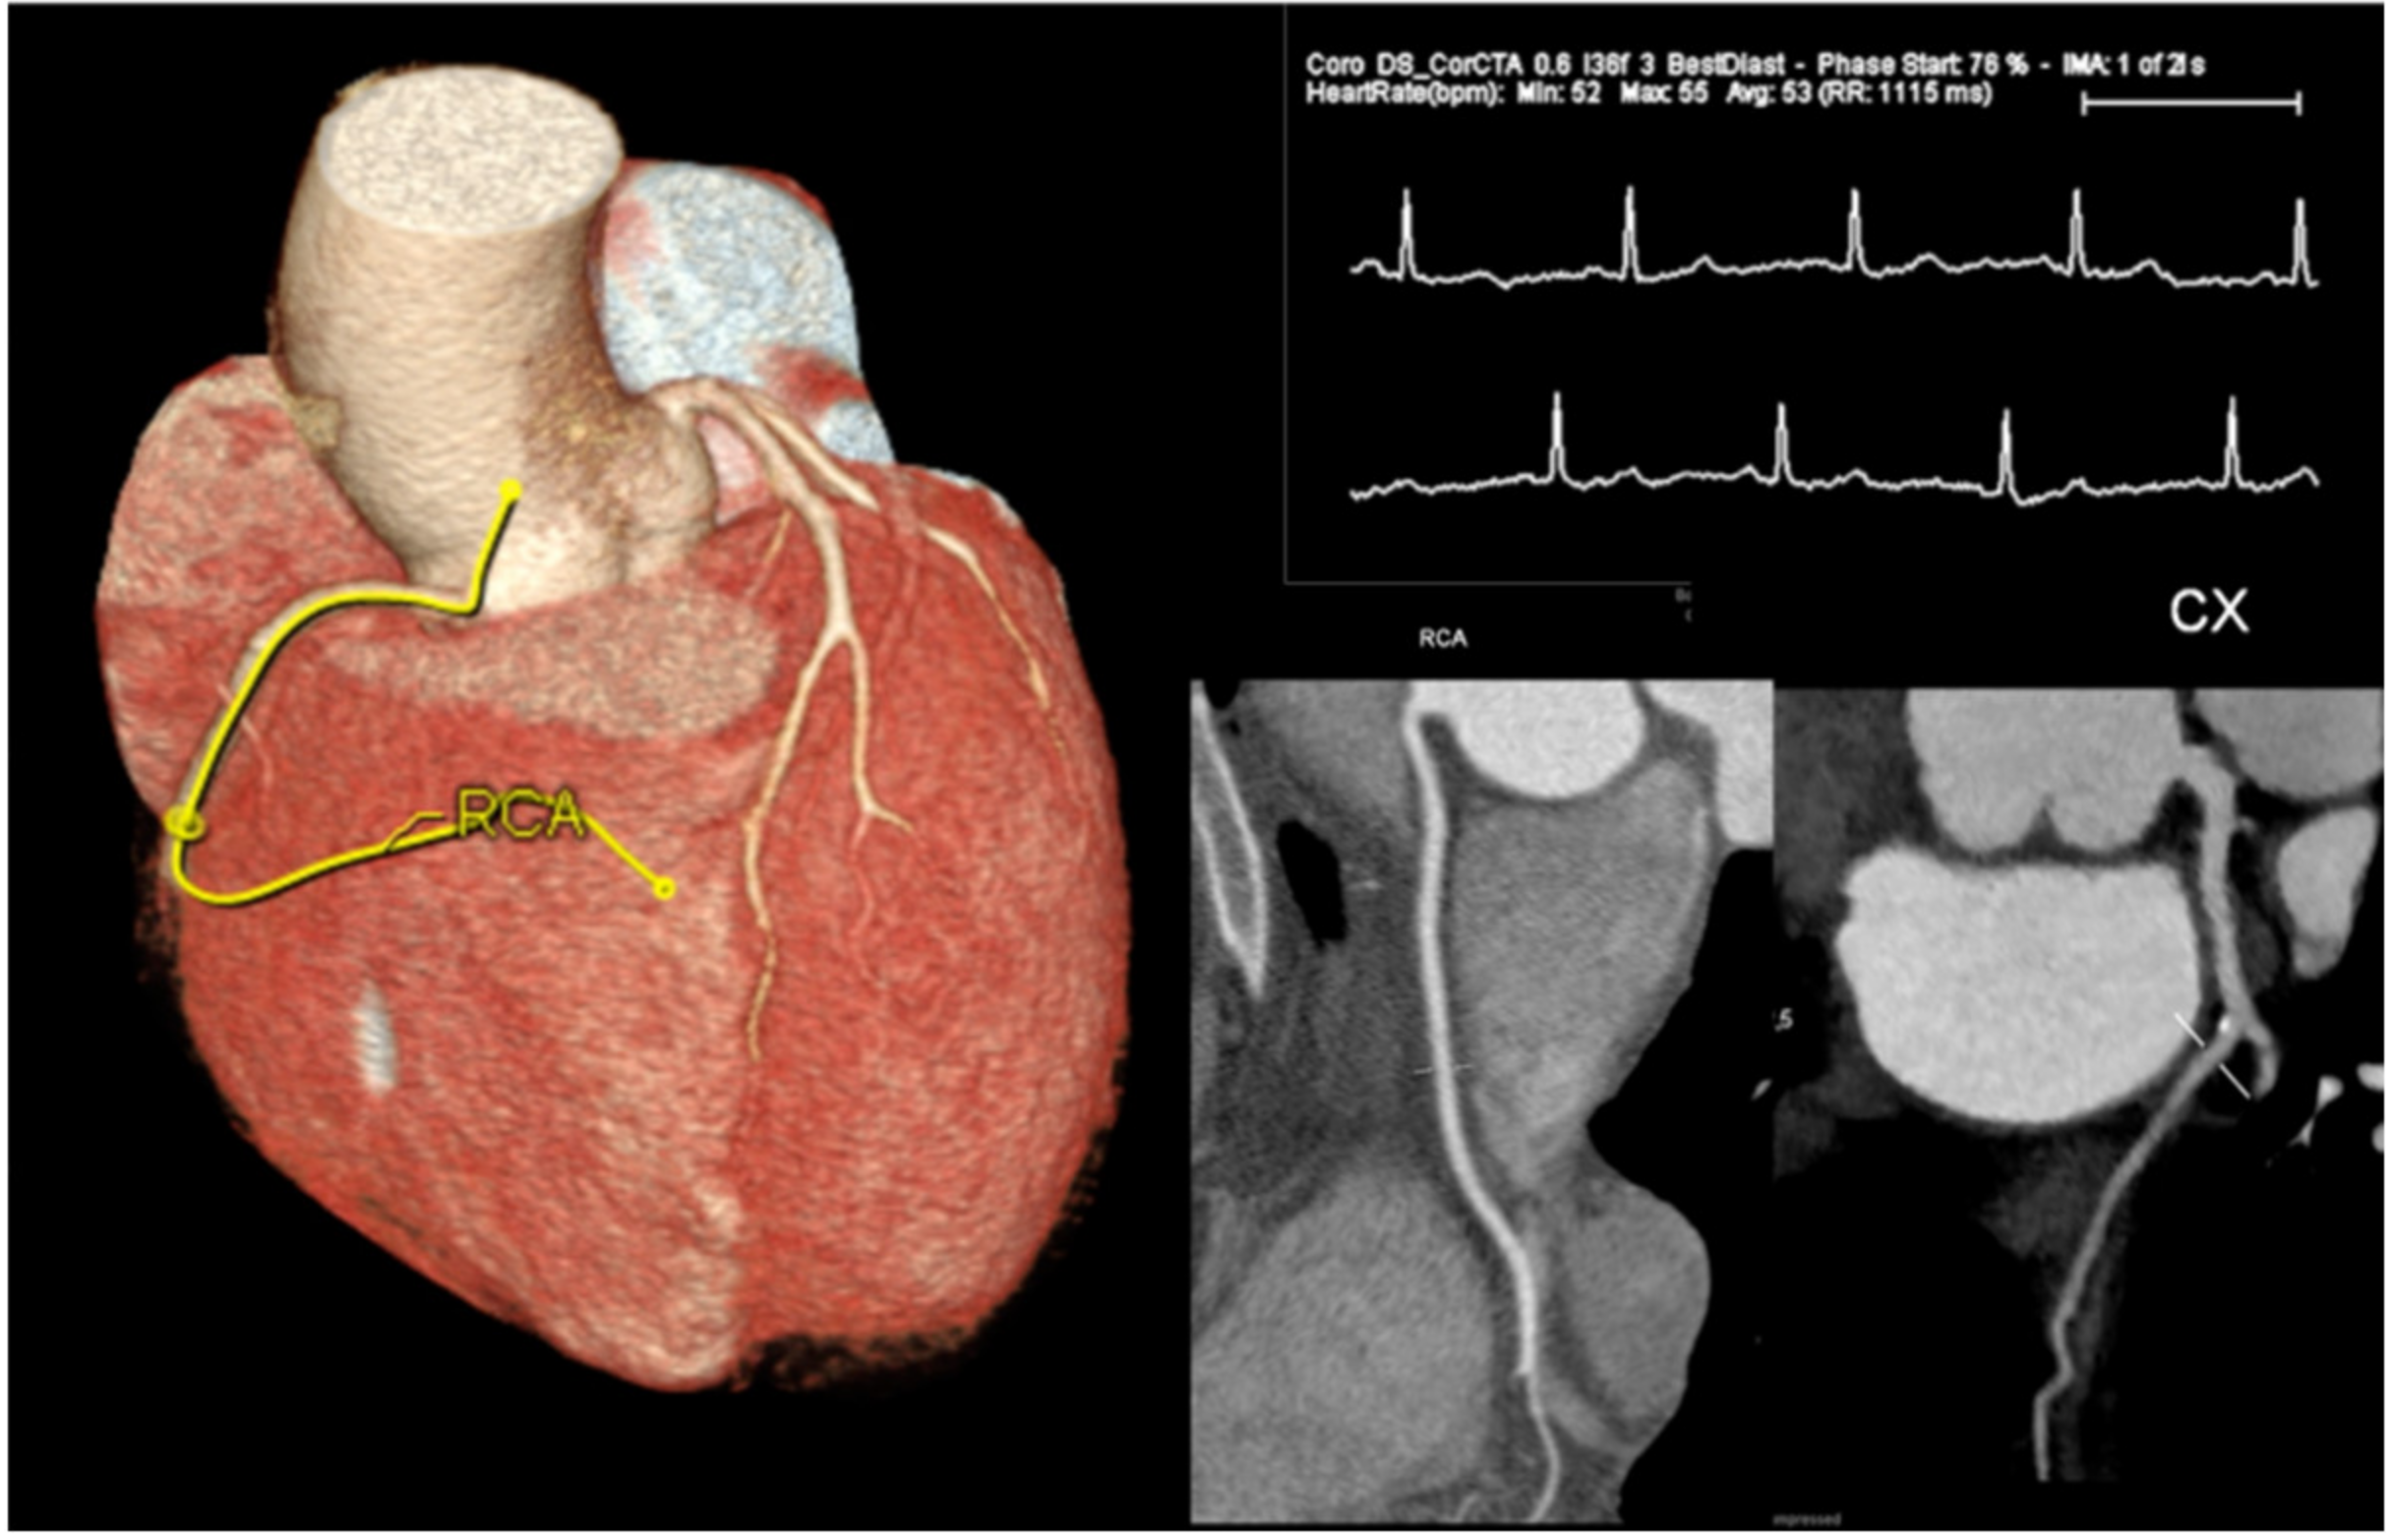

1.2. Role of Coronary CT

- Marano, R.; Rovere, G.; Savino, G.; Flammia, F.C.; Carafa, M.R.P.; Steri, L.; Merlino, B.; Natale, L. CCTA in the diagnosis of coronary artery disease. Radiol. Med. 2020, 125, 1102–1113. [Google Scholar] [CrossRef]

- Busse, A.; Cantré, D.; Beller, E.; Streckenbach, F.; Öner, A.; Ince, H.; Weber, M.A.; Meinel, F.G. Cardiac CT: Why, when, and how: Update 2019. Radiologe 2019, 59. [Google Scholar] [CrossRef]

- Cury, R.C.; Abbara, S.; Achenbach, S.; Agatston, A.; Berman, D.S.; Budoff, M.J.; Dill, K.E.; Jacobs, J.E.; Maroules, C.D.; Rubin, G.D.; et al. CAD-RADSTM Coronary Artery Disease—Reporting and Data System: An Expert Consensus Document of the Society of Cardiovascular Computed Tomography (SCCT), the American College of Radiology (ACR) and the North American Society for Cardiovascular Imaging (NASCI). Endorsed by the American College of Cardiology. J. Cardiovasc. Comput. Tomogr. 2016, 10, 269–281. [Google Scholar] [CrossRef] [PubMed]

- Ramanathan, S.; Al Heidous, M.; Alkuwari, M. Coronary Artery Disease-Reporting and Data System (CAD-RADS): Strengths and limitations. Clin. Radiol. 2019, 74, 411–417. [Google Scholar] [CrossRef] [PubMed]

- Goerne, H.; Landeras, L. CAD-RADS: Pushing the Limits. RadioGraphics 2020, 40, 629–652. [Google Scholar]